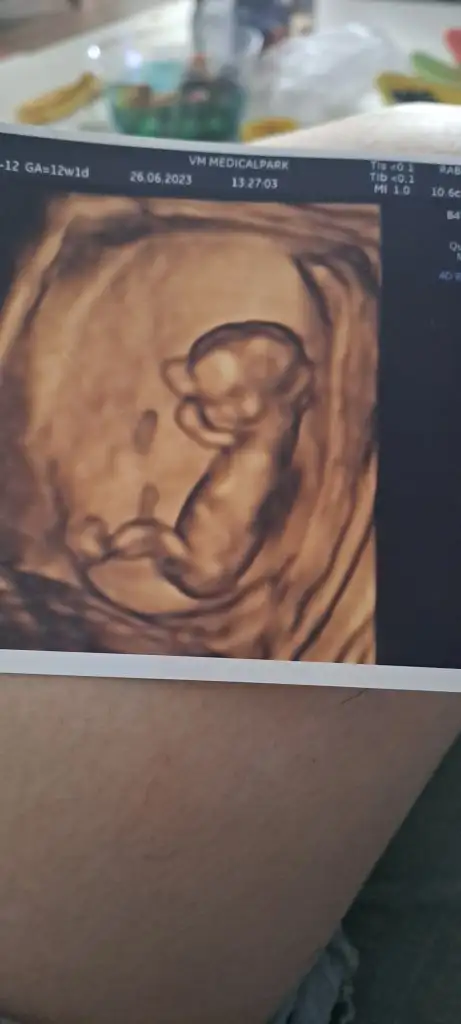

Hanımlar cinsiyet tahmini alabilir miyim 12+1 günlüğüz birde cinsiyeti erkek olanların ultrasyon fotolarını görebilir miyim acaba ocak anneleri benimde 7 ocak dogumum insallah attığım fotolar bacak arası bu arada teşekkür ederim şimdiden

• 20230626_152123.webp

19,9 KB · Görüntüleme: 162

Erkek kuzum

Oğlumun ultrasonu aynı böyle artı çıkıntı bariz belli renkli ultrasonda baksaydı keşke kordon mu diye ama çıkıntı baya belli

Evet nubu aşağıya bakıyormış gibi ama bak bi şişkinlik çıkıntı burda da var

İşte hiç anlamıyorum keşke anlasam ilk bebeğim olcak merak ediyorum sadece. Dr un dedigi ilk %80 90 kız dedi sonra baktı baktı bi çıkıntı gördüm ama bilmiyorum dedi 3 hafta sonra 15 temmuzda netlestircem dedi